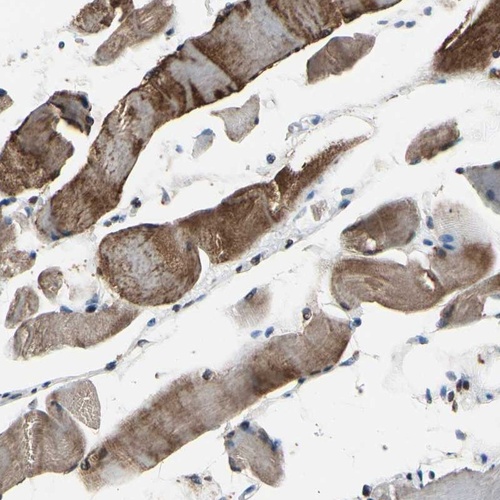

Immunohistochemical staining of human skeletal muscle shows strong cytoplasmic positivity in myocytes.